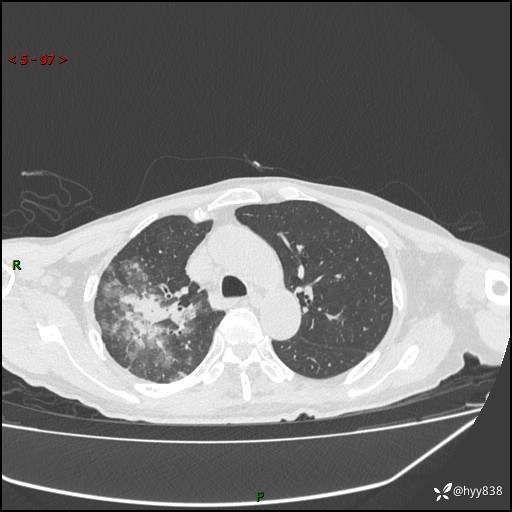

一个月后第二次CT检查(常规抗感染,患者不配合:增强、住院---)